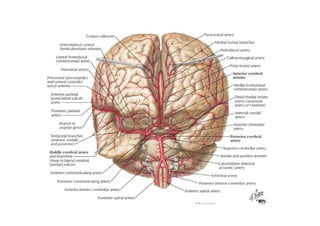

Relações anatômicas e Circulação Arterial

figura

• A artéria vertebral é muitas vezes o primeiro e o maior ramo da artéria

subclávia.

Ela sobre para entrar no forame do processo transverso da 6ª vértebra

cervical. Continua a subir, encerrada nos anéis ósseos formados pelos

forames transversos.

Depois de emergir do forame transverso do atlas, a artéria vertebral

prossegue para curvar-se posterior e medialmente em torno da massa

lateral do atlas.

A artéria vertebral a seguir passa através do forame magno e na borda

inferior da ponte, une-se com a artéria vertebral do lado oposto para

formar o tronco basilar.

As artérias cerebelares póstero-inferiores (ACPIs) saem das artérias

vertebrais imediatamente antes delas se juntarem uma à outra